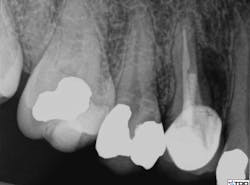

A clinical exam confirmed the presence of a draining sinus tract. Periodontal

probing depths were within normal limits, and the restoration was intact. The radiograph showed previous root canal therapy, post, and crown. A radiographic exam revealed a radiolucent area on the mesial aspect of tooth No. 5 in the coronal third adjacent to the post, as well as a periradicular radiolucency (figure 1).

Figure 1: Radiolucent area on mesial aspect of tooth No. 5 in coronal third adjacent to post, as well as a periradicular radiolucency